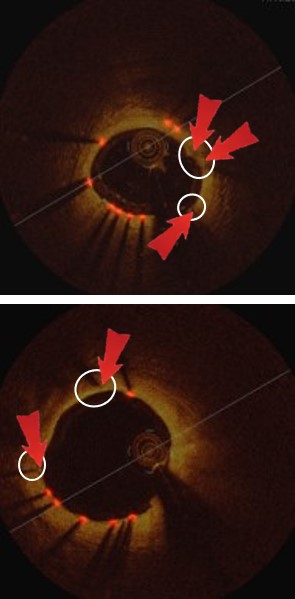

Refer to caption

(a) Image

(b) Labels

(c) F-RCNN

(d) Hong.

(e) Hyeong.

(f) Ours

Figure 4: Comparison of our detection results with existing comparison methods

Table 1 and Fig. 3(a) illustrate our method achieved the overall best performance when compared to the existing methods for strut detection. The traditional methods (Hyeong et al.[7], Hong et al.[5] and Ancong et al.[13]) using hand-crafted features with conventional classifiers achieved competitive performance when compared with Faster-RCNN method. Fig. 4(d) and Fig. 4(e) show two example results where both Hyeong et al and Hong et al methods fail to detect strut points where there is low-contrast to the background. In contrast, Faster-RCNN has the ability to combine deep semantic information and shallow appearance information in a hierarchical manner that enables it to encode image-wide location information and semantic characteristics. However, Faster-RCNN lacks constrain of the overall appearance of all the struts. Consequently, Faster-RCNN generates poor detection results for small struts (as shown in Fig. 4(c)).